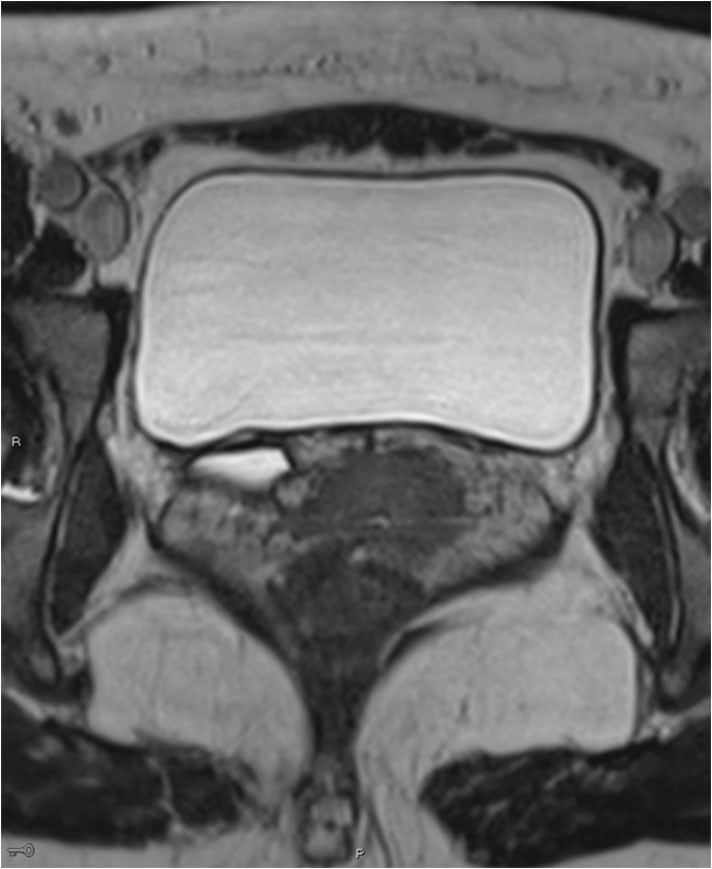

A CT scan of the urinary tract was performed, but proved inconclusive with respect to ureteral ectopia. MRI of the urinary tract was therefore performed in addition. This revealed a right-sided duplex collecting system with a small upper collecting system and a dilated ureter (Figure 1). The ureter was dilated from the bladder to the vagina and opened out ectopically near the urethral opening (Figure 2).

Figure 1 MRI. Coronal 50 mm thick section, T2-HASTE (Half-Fourier Acquisition Single-shot Turbo spin Echo imaging). A right-sided duplex system can be seen, the upper system with moderate hydronephrosis, plus hydroureter in the pelvis.

Identification of a duplex collecting system and ectopic ureter on CT requires adequate function and contrast excretion from the upper collecting system, which was not the case in this patient. It is possible to detect a dilated ectopic ureter with ultrasound, but this can be difficult unless the condition is specifically looked for. Our patient was referred with suspected cholelithiasis and pyelonephritis, and no pathology was detected upon routine examination of the urinary tract. High-resolution fluid-sensitive volumetric MRI sequences are good for identifying the ureter and tracing its course. MRI is more appropriate than CT in the lesser pelvis, but more time-consuming. Dedicated high-resolution series in the pelvis were supplemented with less detailed sequences of the upper urinary tract. No contrast agent was used during the MRI scan. Paediatricians use MRI as the primary imaging modality upon suspicion of ureteral ectopia.